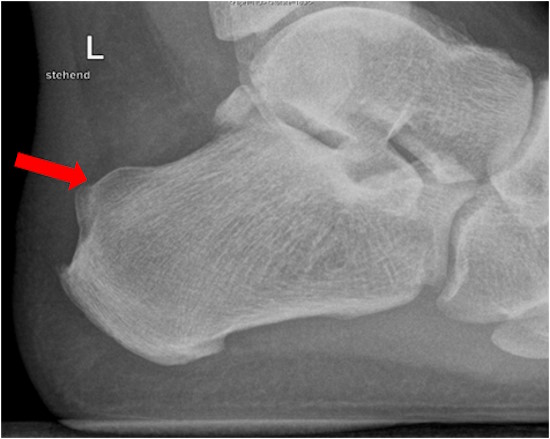

Bildgebende Diagnostik

Ein Röntgenbild des Fußes oder des Fersenbeines im Stand seitlich zeigt dann den vergrößerten Fersenbeinhöcker. Bei V.a. eine Achillessehnenreizung und eine Schleimbeutelreizung können auch eine Sonografie oder eine MRT ergänzend durchgeführt werden.